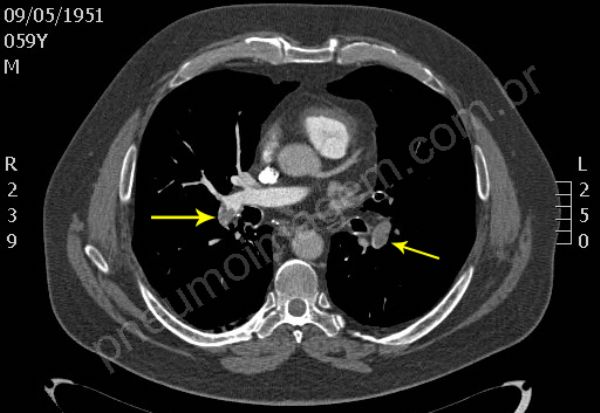

Tromboembolia pulmonar (TEP). Na sequência tomográfica observam-se trombos localizados no tronco da artéria pulmonar e nos principais ramos segmentares à esquerda. Os trombos na bifurcação do tronco pulmonar à direita estendem-se para ramos segmentares do lobo superior, para a interlobar descendente e ramos segmentares do lobo médio. O paciente apresentava também trombose venosa profunda (TVP) na veia femural esquerda, fator de risco importante para TEP. Chaves: tromboembolismo, embolia pulmonar.

Pulmonary thromboembolism (PTE). In tomographic sequence are observed thrombi located in the main pulmonary artery and major segmentary branches left. Thrombi in the bifurcation of the pulmonary trunk right extend to segmentary branches of the upper lobe, extend to descending interlobar and segmentary branches of the middle lobe. The patient also presented deep vein thrombosis (DVT) in the left femoral vein, an important risk factor for PE. Keys: pulmonary embolism (PE).